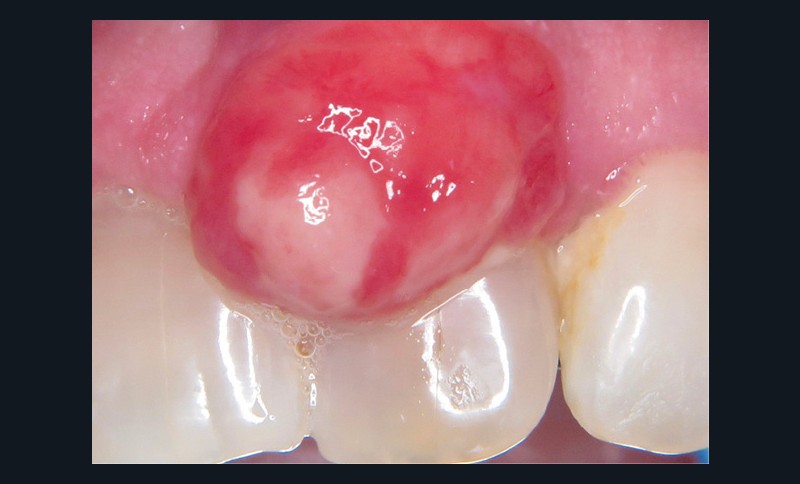

1. Épulis inflammatoire (plasmocytaire)

- Forme gravidique fréquente au 2e et 3e trimestres (fig. 1b). Favorisée par l’augmentation du taux de progestérone, œstrogènes, prostaglandines entraînant une vasodilatation.